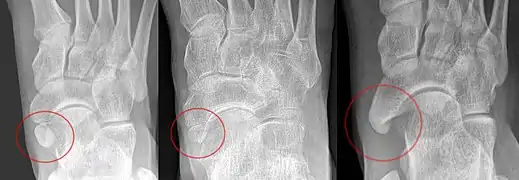

The os ulnostyloideum is an ulnar styloid process that is not fused to the rest of the ulna bone.[6] On X-rays, an os ulnostyloideum is sometimes mistaken for an avulsion fracture of the styloid process. However, the distinction between these is extremely difficult.[6][7] It is alleged that the os ulnostyloideum has a close relationship with or is synonymous with the os triquetrum secundarium.[8]